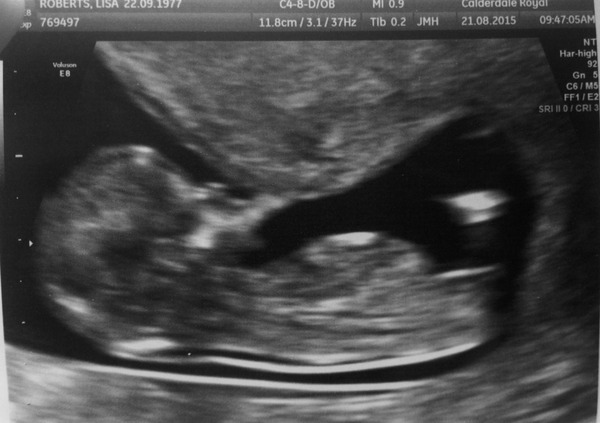

LCR77 · 26/08/2015 08:21

Here you go. Took ages for the sonographer to get this. They wouldn't stay still!

Ah beautiful pic LCR!

Great pic LR.